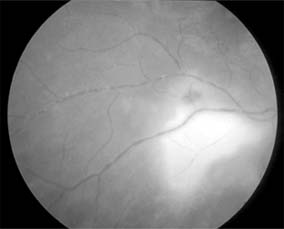

Iritis and iridocyclitis occur in the secondary stage of syphilis along with the rash in about 5% of cases. The inflammation may involve the posterior segment, including the pigment epithelium and the retinal capillaries (Figure 15-28).

Figure 15-28

Figure 15-28: Secondary syphilis. Bilateral visual loss occurred in a 24-year-old man. Late fluorescein photographs showed disk leakage with dilation and leakage of peripapillary capillaries.